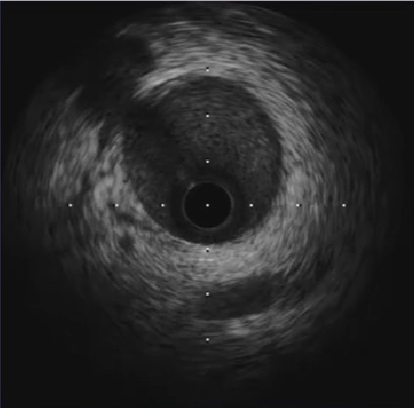

LCX中段大量血栓

LAD中段大量血栓